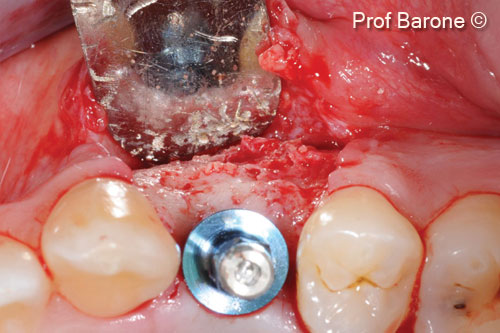

Vật liệu sinh học đã qua sử dụng

Evolution

mp3®